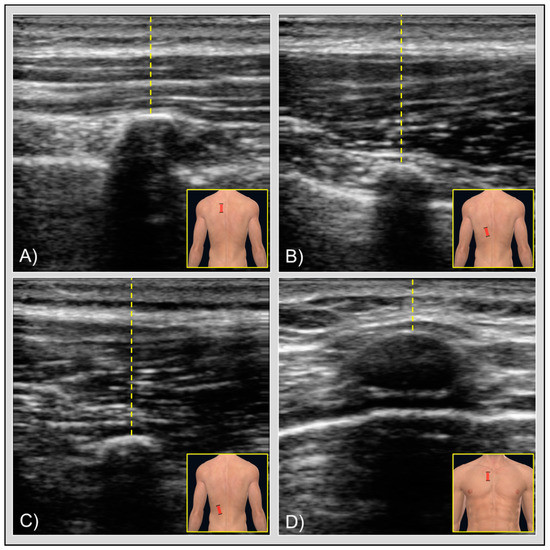

- Rhomboid (Figure 1A): halfway between the medial margin of the scapula and the spinous process of the spine, and halfway between the spine and the inferior angle of the scapula; transducer placed longitudinally.

- Lower trapezius (Figure 1B): 2–3 cm lateral to the spinous process of T8; transducer placed longitudinally.

- Iliocostalis (Figure 1C): 4–5 cm lateral to the spinous process of T10; transducer placed longitudinally.

- Pectoralis major (Figure 1D): lateral to the sternal origin and underneath the clavicular origin of the muscle; transducer placed transversally.